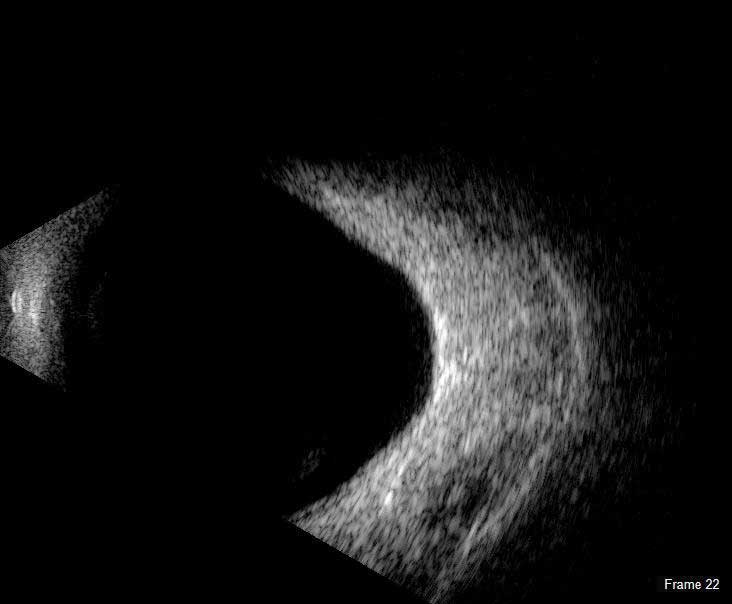

B-Scan

The redesigned B-Scan Probe, new with the Flex, provides clear imaging of the posterior segment of the eye, even when optical clarity is compromised.

The Scanmate Flex B-Scan probe enables clinicians to capture clear and precise images and videos of the posterior segment of the eye. Ultrasonic B-scans are effective, even when opacities (such as dense cataract, blood, or anatomical structures) are present which obscure optical technologies.

The B-Scan probe is available in both 12.5 MHz and 20 MHz frequencies. Among the on-screen tools are calipers to measure structures, an area measurement tool and an annotation tool that gives you a way to indicate pathologies on the image.

B-Scan Diagnostic Applications

The Flex B-Scan delivers clear images of the posterior portion, even when optical clarity is compromised. B-Scan imaging can aid the evaluation of:

- Retinal Detachments

- Vitreous Detachments

- Vitreous Humor Pathologies

- Staphylomas

- Posterior Segment Pathologies

- Choroidal Pathologies

- Optic Nerve Pathologies

- Scleral Thickening